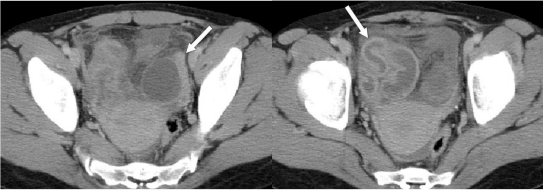

74.28歲女性主訴發燒和下腹疼痛,電腦斷層檢查呈現如圖,箭號所指之敘述何者最正確?

(A)子宮內膜炎 (B)輸卵管卵巢膿瘍 (C)子宮(輸卵管)外孕 (D)子宮頸癌